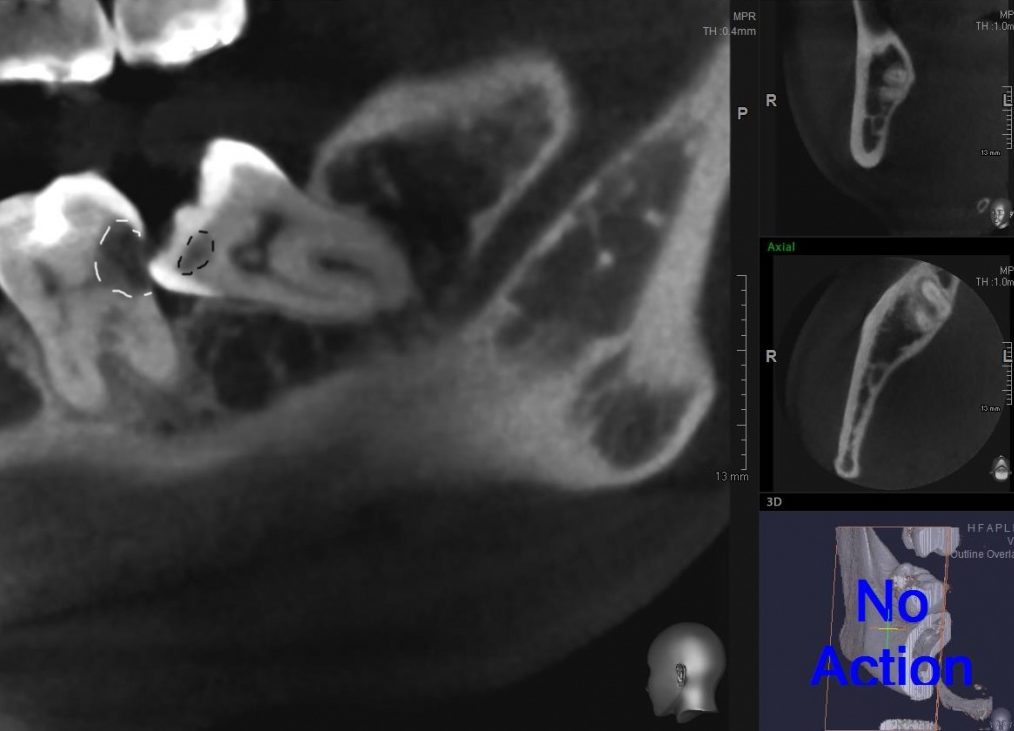

Сегодня я покажу вам, уважаемые друзья, один снимок. Это зуб мудрости, на удаление которого мы потратили, в общей сложности, около 7 минут:

На снимке белым пунктиром выделена кариозная полость седьмого зуба (острая боль в котором, собственно, послужила причиной удаления). Черным пунктиром — кариозная полость восьмерки.

Посмотрите на этот снимок. Подумайте.